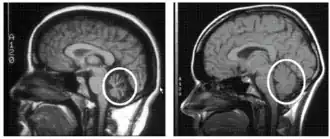

Cerebellum (labeled bottom right) of the human brain. It is located above the brain stem, posterior to the brain. | |

To select an appropriate and accurate diagnostic test for cerebellar degeneration, it is crucial that a range of factors specific to each patient are taken into consideration. These include; the patient's age, acuity of their signs and symptoms, associated neurological conditions, and family history of hereditary forms of cerebellar degeneration.[3] A diagnosis for cerebellar degeneration is regarded after any of the aforementioned signs and symptoms surface. For genetically classified forms of cerebellar degeneration, genetic testing can be carried out in order to confirm or deny the diagnosis, where this form of testing is only possible if the gene responsible for the cause of the condition is recognised.[24] In saying this, for most conditions the genetic cause of cerebellar degeneration is unidentified, hence these patients cannot proceed with genetic testing.[1] In cases where cerebellar degeneration is acquired, a diagnosis can be established using imaging methods such as computerised tomography (CT scans) and magnetic resonance imaging (MRI), necessary to detect brain abnormalities in patients with cerebellar degeneration.[25]